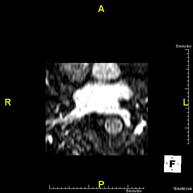

- URO-RM

Prueba diagnóstica no invasiva que consiste en la obtención de imágenes de alta definición anatómica del sistema urinario mediante el empleo de un campo electromagnético y ondas de radio (con un emisor y un receptor). No utiliza radiación ionizante. Requiere el uso de contraste paramagnético (Gadolinio) que se excretará por el sistema urinario y nos permitirá obtener imágenes en 2D y 3D. - RM Próstata